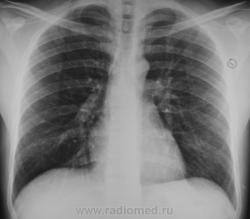

Правый КДС и лег рис справа - немного заинтерсовали. Но для грыжесечения, думаю, значения не имеют. "Норма" --->> "По месту .... сравнить с Фл-архивом".

А почему снимок такой "темный"? Почему лопатки полностью наслаиваются на легочные поля. Может лаборант выполняет укладку установку пациента не правильно?

Обратите внимание на первое ребро.

Обратили.На фоне ребра не совсем понятные полостюшки( полостями язык не поворачивается назвать).

Для начала я бы убедился, что это не артефакт и не игра теней.

Не исключено , что в ребре литические очаги .

Это не артефакт, на самом деле в 1-ом ребре есть литический очаг.